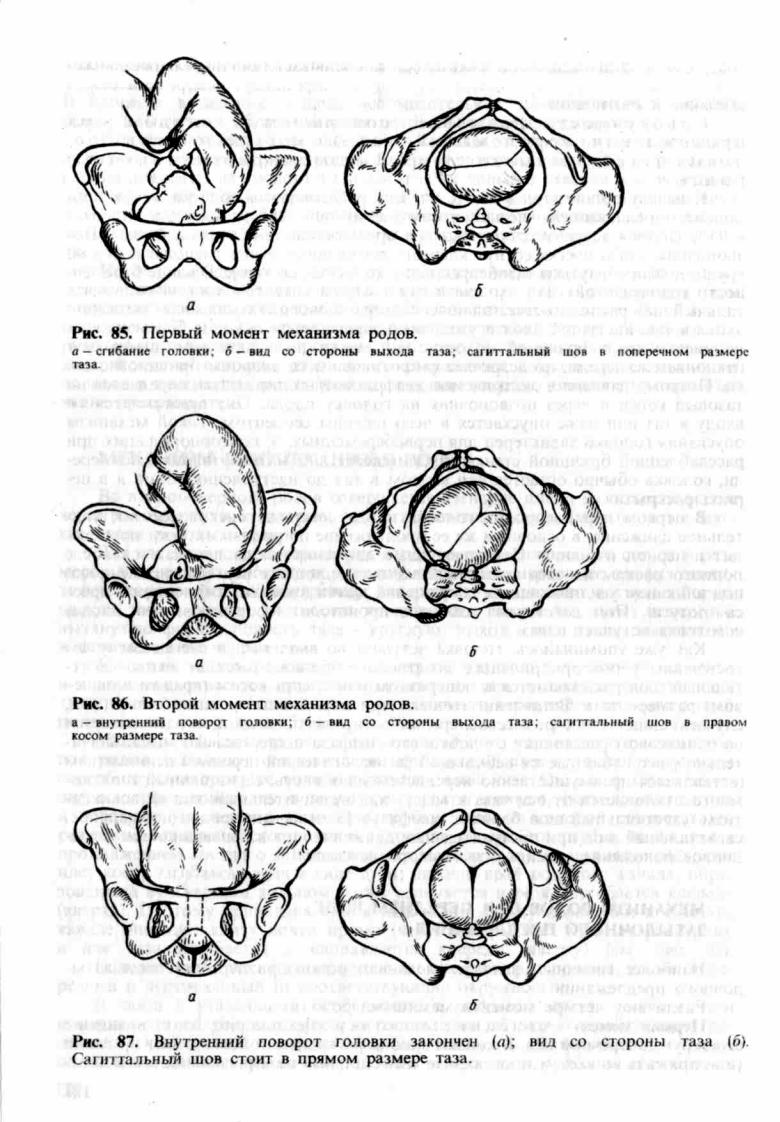

Задний вид затылочного предлежания биомеханизм родов

Биомеханизм родов в переднеголовном предлежании

Стрелоаидный шов вправом косом размере

Передний асинклитизм биомеханизм родов

Биомеханизм родов таблица

Биомеханизм родов таблица

Первый момент биомеханизма родов при тазовом предлежании